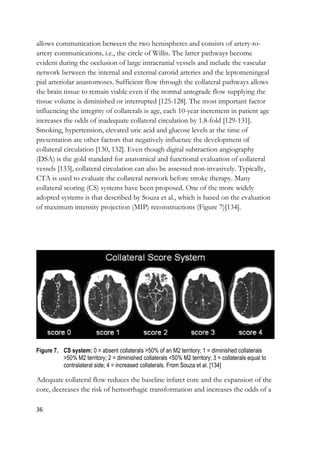

collateral scoring (CS) systems have been proposed. One of the more widely

adopted systems is that described by Souza et al., which is based on the evaluation

of maximum intensity projection (MIP) reconstructions (Figure 7)[134].

Figure 7. CS system: 0 = absent collaterals >50% of an M2 territory; 1 = diminished collaterals

>50% M2 territory; 2 = diminished collaterals <50% M2 territory; 3 = collaterals equal to

contralateral side; 4 = increased collaterals. From Souza et al. [134]

Adequate collateral flow reduces the baseline infarct core and the expansion of the

core, decreases the risk of hemorrhagic transformation and increases the odds of a

37

good clinical outcome in-hospital, at discharge and six months after the stroke.